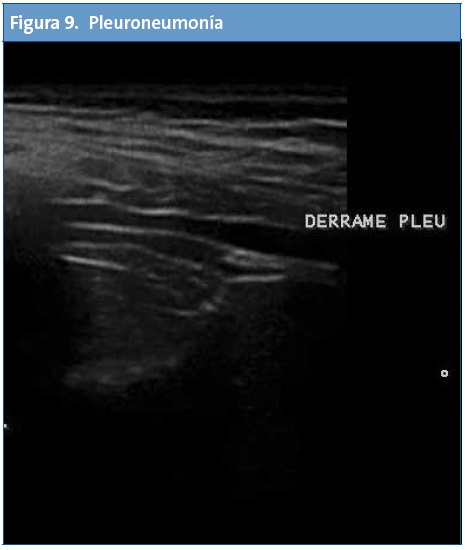

En Atención Primaria el mayor rendimiento se obtiene de la exploración abdominal seguida del estudio de la zona cervical, partes blandas, aparato genital, pulmón y aparato locomotor.